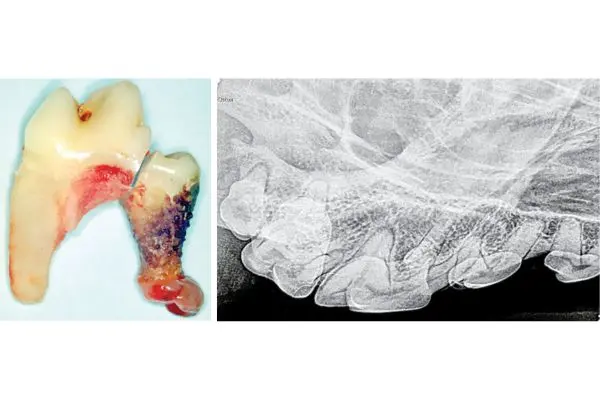

Have you heard of the chevron lucency?February 3, 2026Interpreting dental radiographs in dogs and cats can be challenging, particularly when assessing teeth for possible endodontic disease. This column discusses the classic radiographic signs individually.